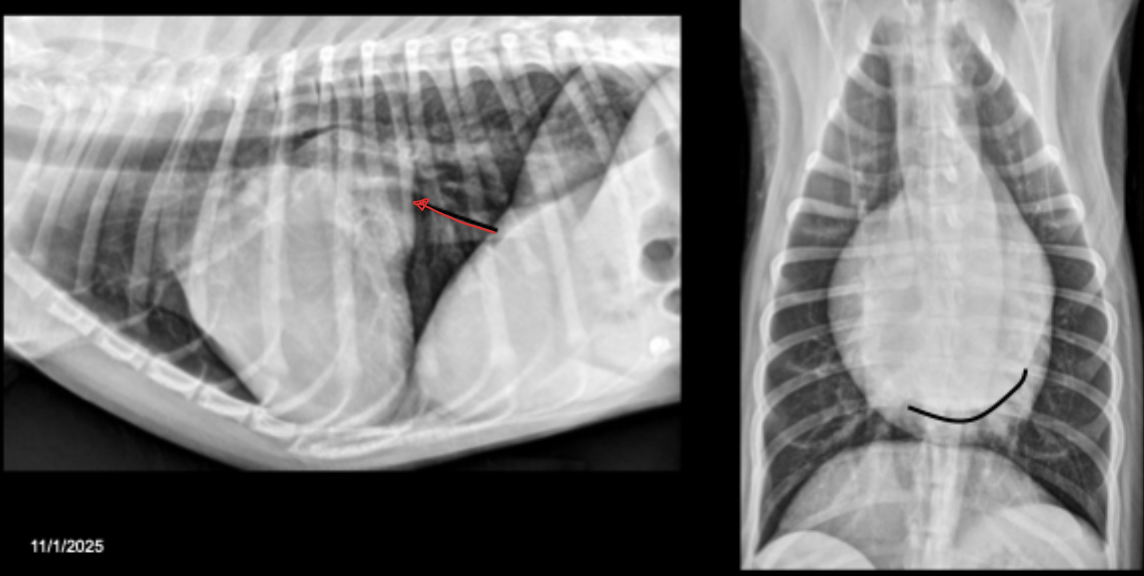

What can be seen in this canine radiograph?

pericardial effusion

What are abdominal manifestations of pericardial effusion?

dilated CVC

hepato-splenomegaly

ascites

What border description of the heart can be associated with pericardial effusion?

curved caudal dorsal border